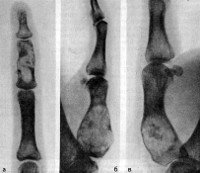

Заболевание проявляется отставанием роста и деформацией пораженных сегментов. Часто наблюдаются патологические переломы. На рентгенограммах длинных трубчатых костей выявляются колбовидные увеличения метафизов при неизмененных диафизах. Нормальный костный рисунок в зоне метафизов отсутствует, вместо него определяется неравномерно исчерченное просветление. Корковый слой истончен. На рентгенографии кистей и стоп видны укорочение и деформация фаланг. Просветления локализуются в центральных отделах, корковый слой, как правило, не изменен, при энхондромах больших размеров наблюдается вздутие кортикальной пластинки.

Диагностика энхондром, как правило, несложна. На рентгенограммах длинных трубчатых костей выявляется центрально расположенное облаковидное просветление. В зоне просветления могут обнаруживаться более темные участки - очаги кальцификации. Опухоли в области коротких трубчатых костей обычно выглядят однородными и занимают большую часть поперечника или весь поперечник кости. Кортикальный слой не нарушен. На КТ кости определяется аналогичная картина, преимуществом компьютерной томографии является возможность более подробно рассмотреть структуру энхондромы.